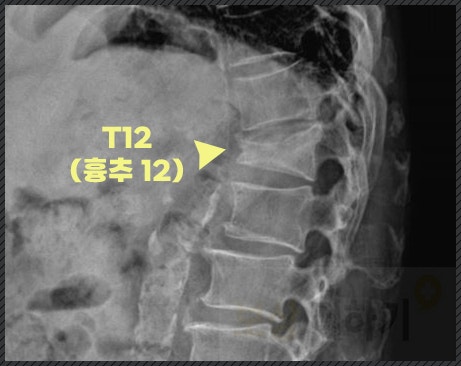

실제 사례 합의금 1천만 원 이상 흉추 12번 골절

실제 사례를 한 번 살펴보실까요? S 님은 아파트 엘리베이터에서 내려 발을 딛는 순간 미끄러져 뒤로 넘어지셨습니다. 알고 보니 그날은 비가 와서 빗물이 엘리베이터 앞에 고여 있었던 것이죠.

▶ 흉추 12번 골절 ▶ 보존 치료 이 과정에서 흉추 골절이 되었고, 몇 개월 보조기 착용을 하셔야 했습니다. 다행히 아파트 측 과실이 인정돼 배상책임보험 접수는 무사히 이뤄졌습니다. "치료비 정도만 준다고.." 전문가의 개입 결과는? 접수는 잘 됐지만 이후 더 큰 문제, 바로 보험사에서 제시한 금액이었는데요. 200만 원도 안 되는 합의금에 억울한 마음과 걱정이 몰려와 너무 힘드셨다고 해요. 저희 『보상 더하기』 손해 사정사는 S 님의 부상 정도와 생활상의 불편을 객관적으로 입증해 재산정을 요청했고, * 최초 제시액의 약 7배에 달하는 보상으로 합의를 이끌어낼 수 있었습니다. ▼합의금 산정 시 중요한 자료